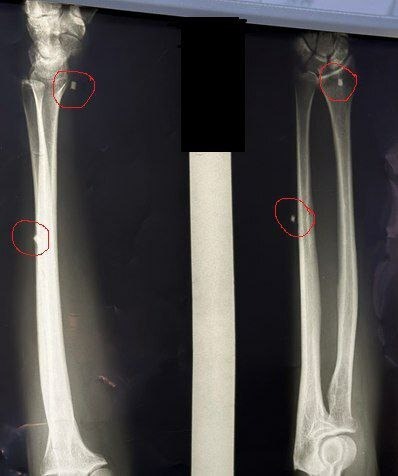

В городской больнице Салавата провели уникальную операцию участнику специальной военной операции из Кугарчинского района.

Как сообщили в минздраве республики, боец получил ранение во время подрыва в зоне СВО.

Операцию провёл нейрохирург Арслан Асылбаев. В настоящее время боец проходит реабилитацию, подвижность руки восстанавливается, уточнили в ведомстве.